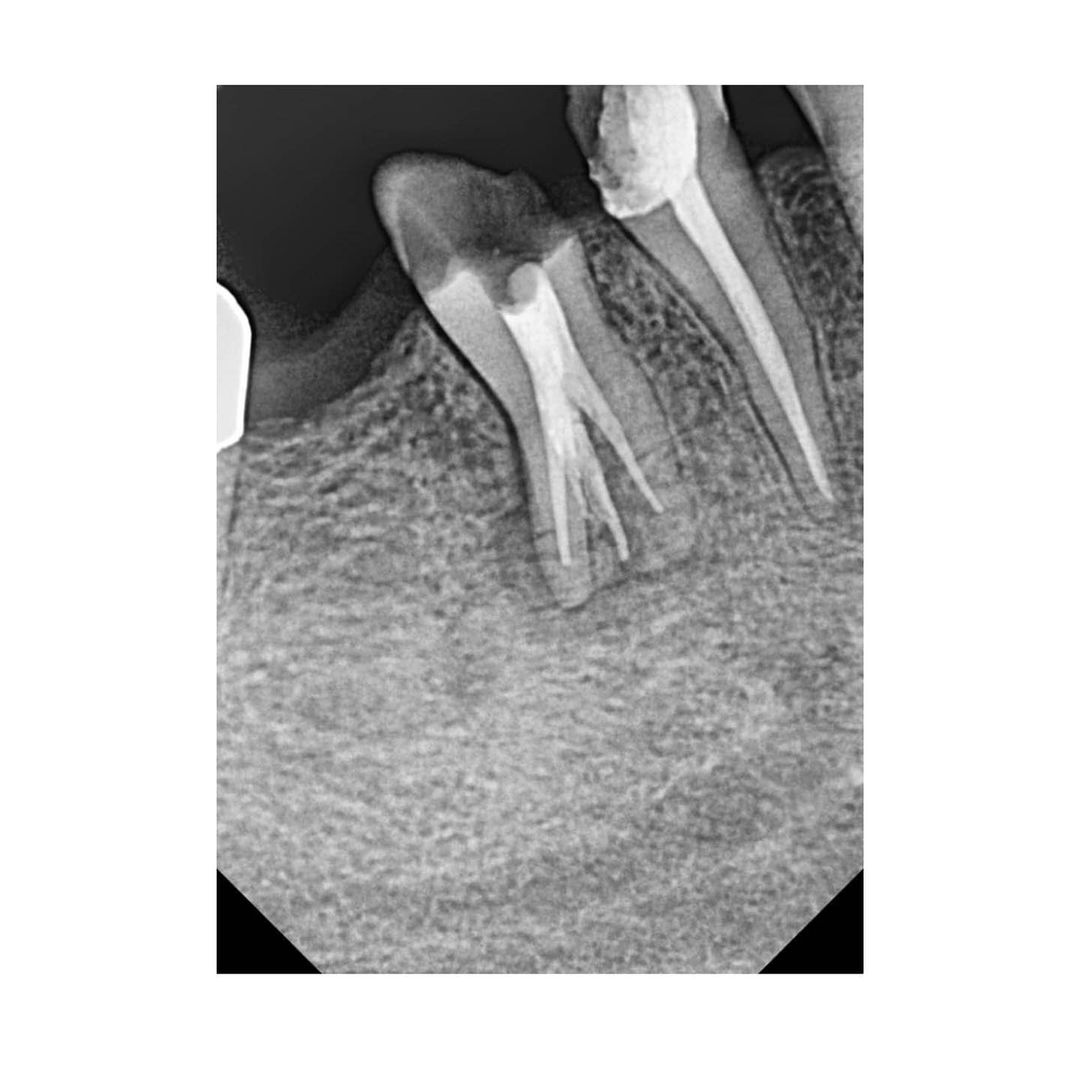

Collection of 3-canal lower premolar.

Collection of 3-canal lower premolar.